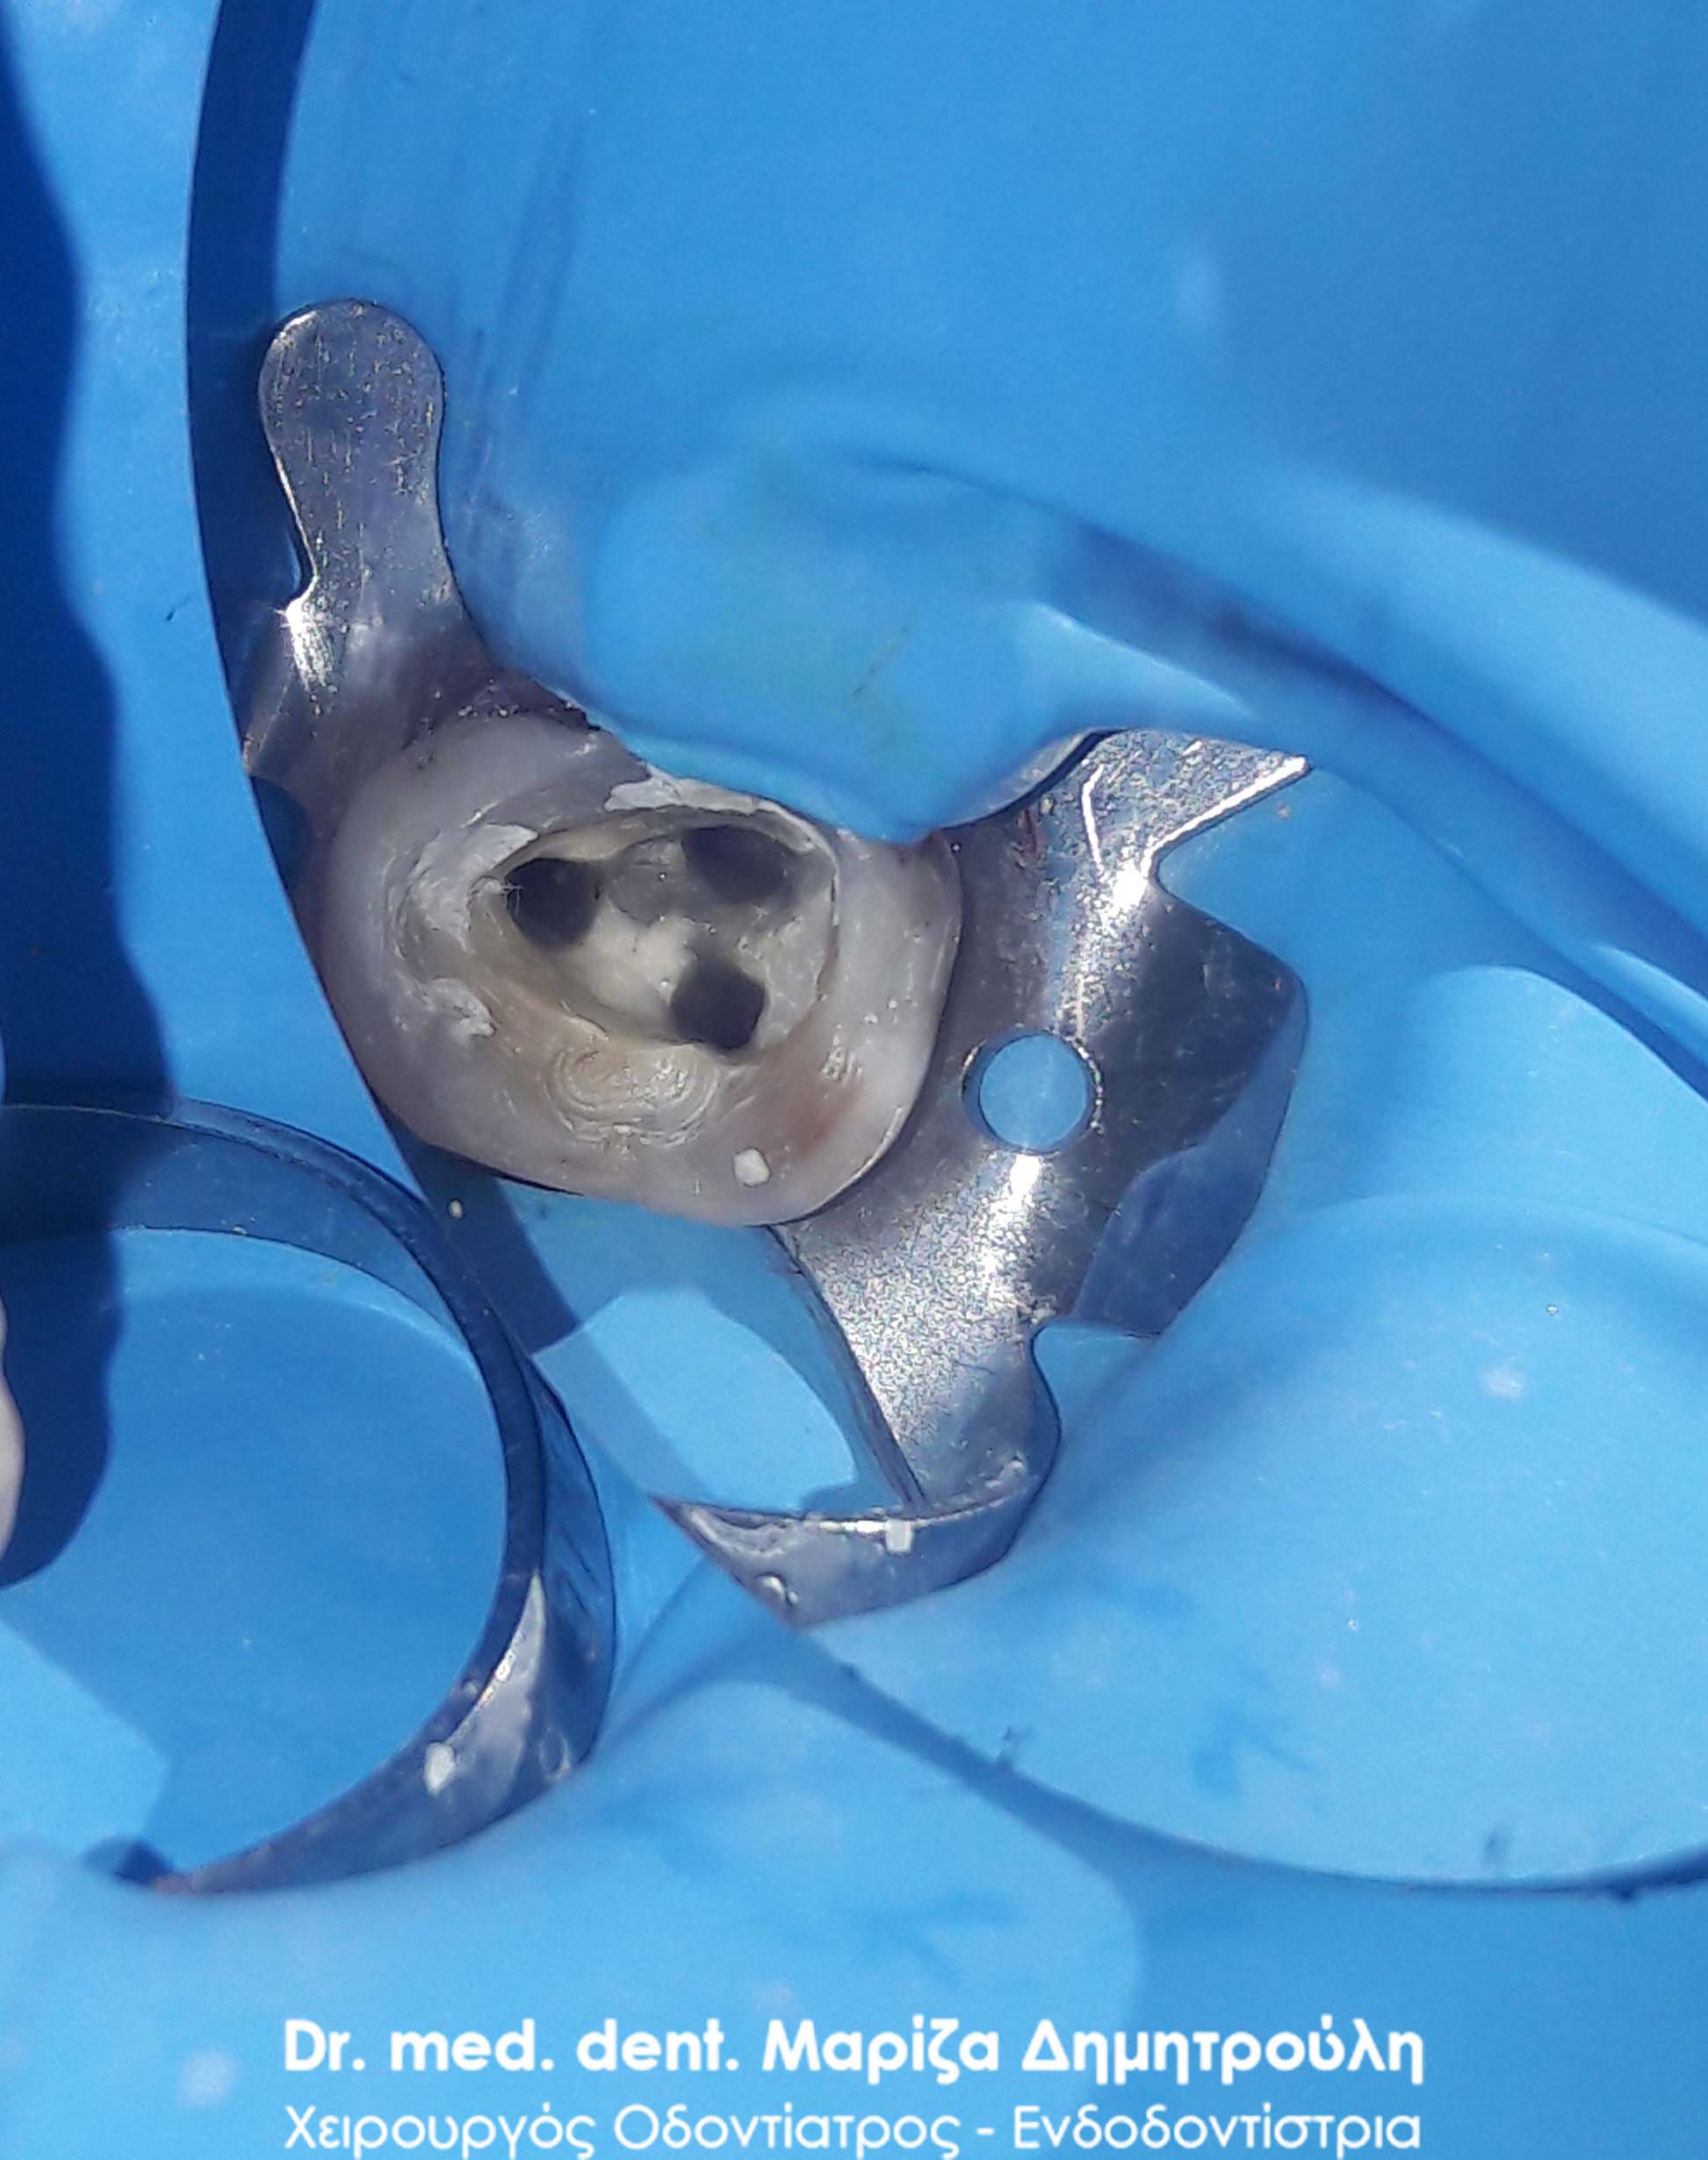

Clinical photo after the root canal filling